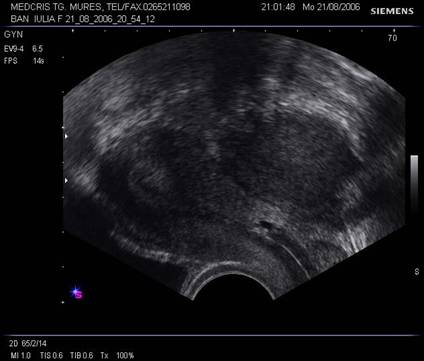

Fig. nr.393. Chist ovarian inomogen, cu hemoragie intrachistica , la ecografia transvaginala. ( la o luna remis spontan )